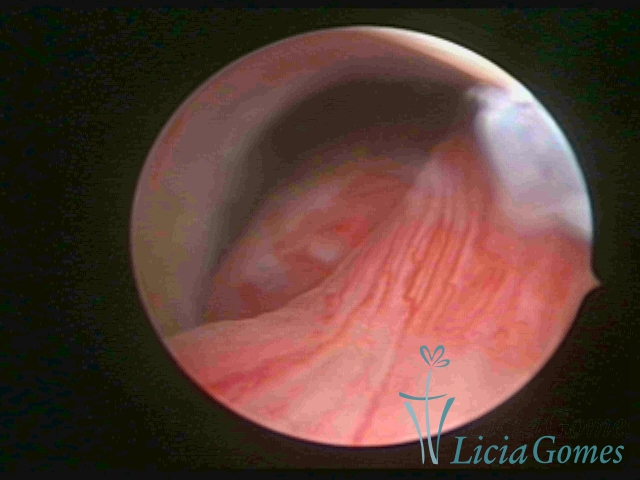

ENDOCERVICAL POLYPS

Benign tumors resulting from the reactive focal proliferation to inflammatory processes or hyperestrogenism situations, which may be sessile (with a large implantation) or stalked.